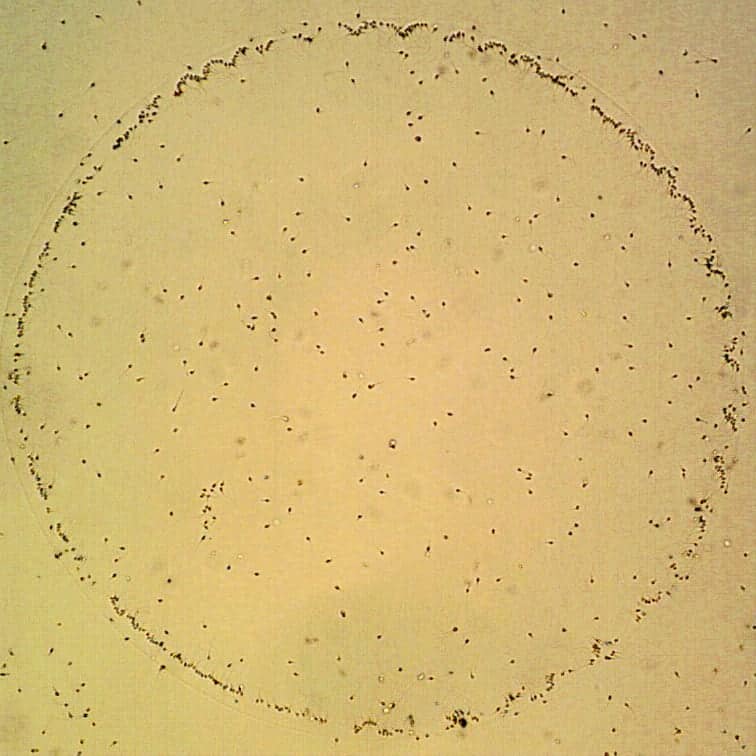

Pri tejto metóde sú spermie inkubované v Petriho miske, ktorej dno je pokryté hyaluronanom. Pre ICSI sú následne vyberané iba spermie naviazané na hyaluronan. Hyaluronan je mukopolysacharid, ktorý sa prirodzene vyskytuje ako súčasť medzibunkovej hmoty obklopujúcej spolu s kumulárnymi bunkami vajíčko. Aby mohla spermia pri prirodzenom oplodnení úspešne preniknúť do vajíčka a oplodniť ho, musí byť schopná viazať sa k hyaluronanu. Takéto interakcie je schopná iba zrelá spermia. Vedeckými štúdiami bolo potvrdené, že spermie, ktoré sú schopné väzby k hyaluronanu, majú lepšiu morfológiu, štatisticky nižší podiel chromozomálnych anomálií a lepšiu integritu DNA.